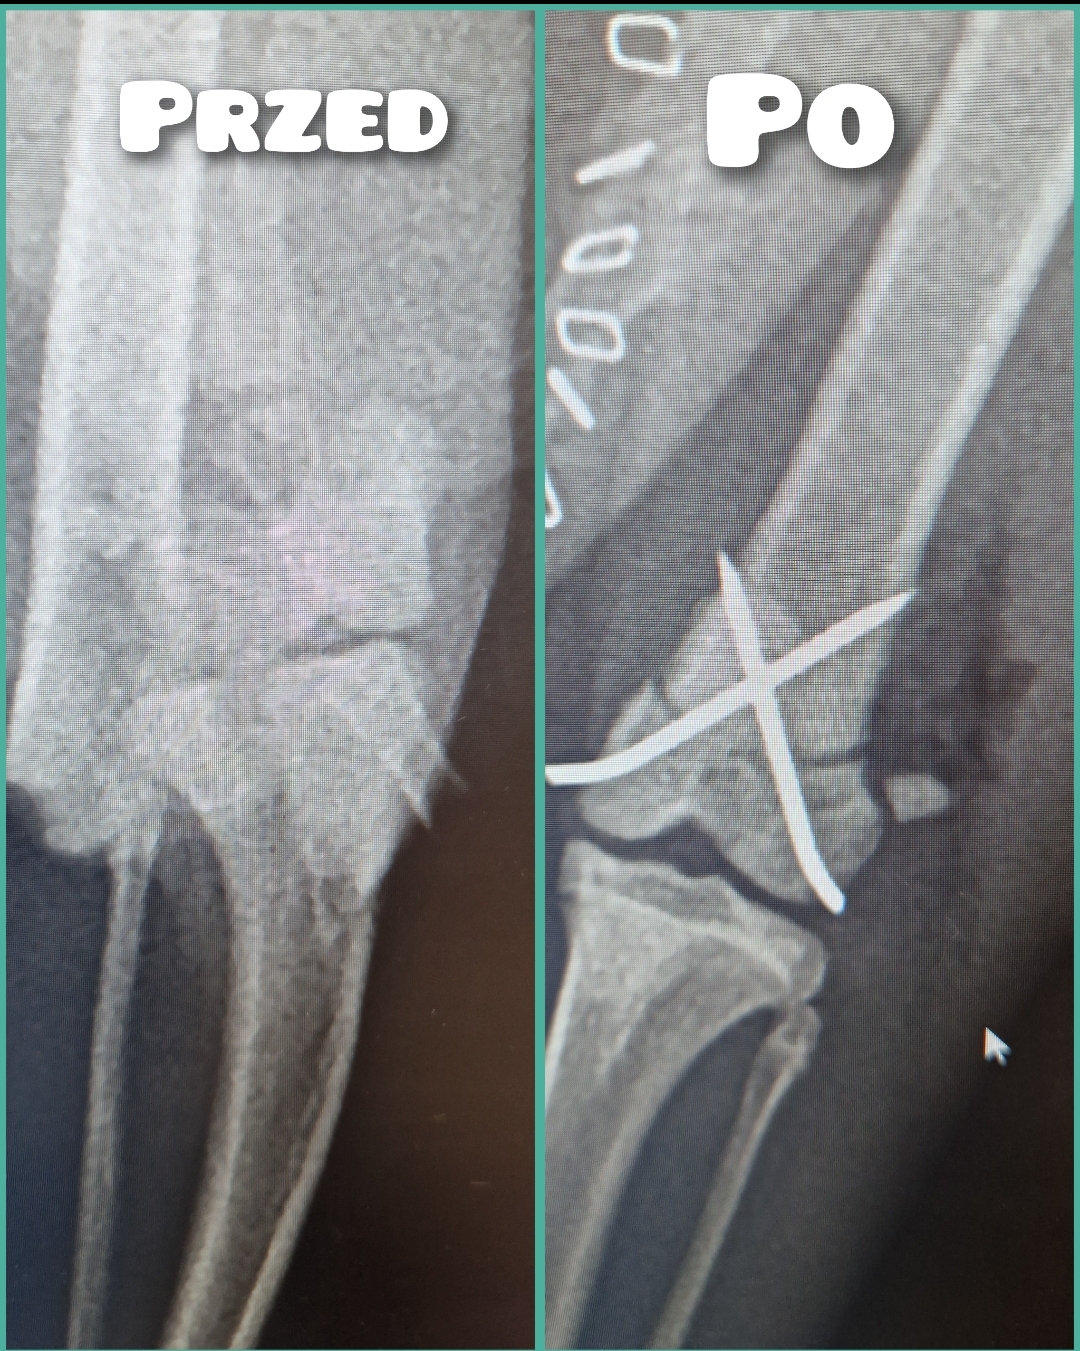

Jest szansa na uratowanie Bajki, ma złamaną prawą tylną łapką i pogruchotaną w kilku miejscach miednicę. Niestety - nasze możliwości finansowe się wyczerpały, życie dość mocno sie ze mną obeszło w ostatnich latach i nie mam generalnie nic. Dziś wydaliśmy wszystkie skromne oszczędności, żeby opłacić leczenie Bajki do tej pory.

Kochani, dzięki Waszym wielkim sercom Bajka dziś pomyślnie przeszła operację - DZIĘKUJEMY ????♥️???? Wielkie brawa dla lekarzy z lecznicy Cztery Łapy w Jeleniej Górze ! Koszt operacji wyniósł 3260 PLN plus każdorazowa wizyta kontrolna 30 PLN plus koszty dodatkowe za miesiąc, tj. wyjęcie śrub, leki, rehabilitacja. Dziś zapłaciłem 3000 PLN, załączam rachunek. Następne załączę przy kolejnych opłatach. Bajka wysyła miaubuźki (. ❛ ᴗ ❛.)